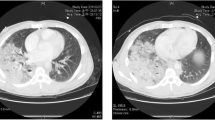

On the third day post-trauma, the patient developed ACS (intraabdominal pressure >30 mm H2O, as measured using a pressure transducer in the urinary bladder, which had been filled with 100 mL of NaCl). Renal function was impaired (oliguric), and lung compliance deteriorated extensively and rapidly within an hour (tidal volume less than 50 mL on ventilator settings with PEEP 15 and inspiratory pressure of 35 cm H2O). Exploratory laparotomy was performed at the patient’s bedside. The renal function had improved, but lung compliance had not. Postoperatively, the ventilator was disconnected, and the endotracheal tube was left blocked in the trachea, with a T-piece placed at the end of the tube. Thus, gas exchange was achieved through VV ECMO alone. During the next 48 h, the patient’s sedation was weaned and respiratory effort (thorax movement) was observed. The spontaneous breaths were sporadic, occurring at a rate less than 10 per minute, and very shallow. Percutaneous dilatational tracheotomy was performed. Subsequently, assisted ventilation with very low tidal volumes (20–30 mL) was initiated. No atelectasis was present. The patient’s lung compliance increased to 300 mL over the following 3 days. The patient was weaned from VV ECMO and mechanical ventilation on days 9 and 13, respectively, after the trauma (Fig. 1). He was discharged from the ICU after 16 days and from the hospital after 49 days. His recovery and outcome after 12 months follow-up revealed no neurological disability.